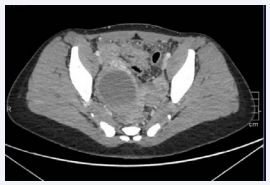

The patient received parenteral antibiotics with Doxycycline and Metronidazole and her physical condition improved day by day as she did not have any fever and her abdomen was less painful. Meanwhile, the level of GL kept decreasing. However, on Post-Operative Day [POD] 5, due to abdominal pain recurrence andthe rising of the GL up to 19*10^3/ml, a new abdomino-pelvic CT was completed and revealed increasing of the right ovarian cyst’s size with a diameter of 7,5cm compatible with an ovarian abscess (Figure 1,2).

Right ovarian abscess on the first abdomino-pelvic CT (cuts: 1,25mm) with contrast (left) and the same increased size abscess on the second CT with contrast (right).

Figure 1: Right ovarian abscess on the first abdomino-pelvic CT (cuts: 1,25mm) with contrast (left) and the same increased size abscess on the second CT with contrast (right).

Right ovarian abscess on the first abdomino-pevic CT with contrast (cuts: 1,25mm).

Figure 2: Right ovarian abscess on the first abdomino-pevic CT with contrast (cuts: 1,25mm).